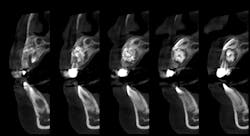

A panoramic film (figure 1) taken by the general dentist revealed a large radiodense area in the region apical to teeth D and E. The patient was referred to an oral and maxillofacial surgeon who obtained a CBCT scan (figure 2).

Clinical and radiographic assessment revealed retained primary teeth D and E, and buccal cortical expansion over the apices of these teeth. A cone beam CT scan revealed a well circumscribed, mixed radiodensity overlying the apices of the primary teeth, adjacent permanent teeth nos. 7 and 8 displaced in a caudal direction, and cortical expansion.

The patient, under intravenous anesthetic, underwent enucleation of the lesion with simultaneous extraction of primary teeth D and E. An intraoral approach was used, the labial cortex was removed, and the mass was removed intact via simple enucleation (figures 3 and 4). The crowns of permanent teeth nos. 7 and 8 were visualized within the cavity of the enucleated mass. No grafting was performed, and the wound was closed primarily in simple fashion.

Gross examination of the specimen revealed multiple calcified structures resembling deformed teeth of various sizes within the mass, confirming the clinical suspicion of compound odontoma (figure 5). Two subtypes of odontoma are recognized: compound odontoma and complex odontoma. The compound odontoma is made up of multiple structures of dentin and enamel resembling supernumerary teeth. A complex odontoma consists of a mass of dentin and enamel without the anatomical appearance resembling teeth. The histopathologic report also confirmed the clinical suspicion of compound odontoma.